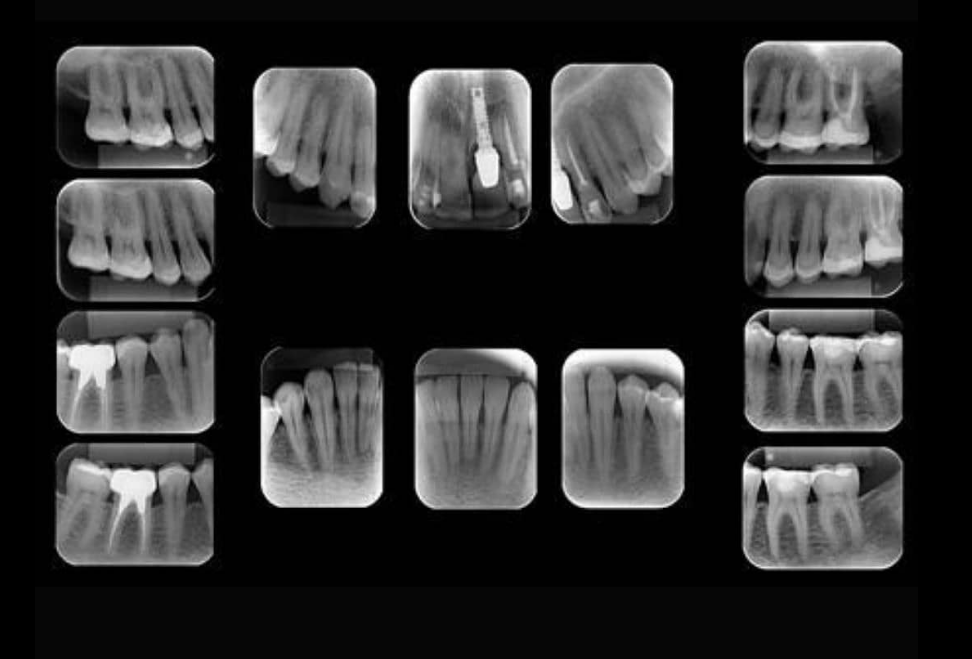

Radiografia Periapical

Imagem de alta precisão para diagnóstico de estruturas dentárias e periapicais

A radiografia periapical é um exame fundamental para a análise detalhada de um ou mais dentes, permitindo a visualização completa da coroa, raiz, ligamento periodontal e osso alveolar. Seu alto nível de detalhamento possibilita o diagnóstico de lesões periapicais, adaptação de restaurações e avaliação da resposta óssea a tratamentos odontológicos.

Muito utilizada em endodontia, periodontia e odontologia restauradora, a radiografia periapical é indispensável para o acompanhamento clínico e tomada de decisões em procedimentos minimamente invasivos.